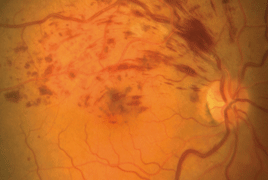

- Subjektívne zmeny vo videní u pacientov s diabetickým makulárnym edémom liečených ranibizumabom

- Postradiačná makulopatia u pacientov s malígnym melanómom corpus ciliare a chorioidey po stereotaktickej rádiochirurgii